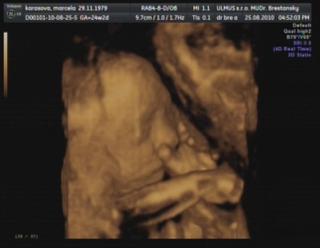

Dnes sme boli na to 4D v HC. Som v 24+2 tt, Patrik má 631g a v kuse si cmúľal palček, alebo obzeral ruky. Všetko je v poriadku čo sa týka malinkého, srdiečko mu bije 148 úderov za minútu 😉 Termín polovica decembra sedí, cca 16.12.2010. Aj v H mi povedal, že zatiaľ to vyzerá na cisársky kvôli placente, ale že to sa ešte môže upraviť. No to je jedno, dôležité je, že všetko je tak, ako má byť 🙂

Bol s nami aj Erik, ten to prežíval, rozprával Patrikovi nech si nedáva prsty do pusy 😀 Podarený bol.

S Erikom som bola tiež v HC, ale trochu skôr, v 23+6 tt, a vážil vtedy 667g. Sranda, bo trošku ťažší...